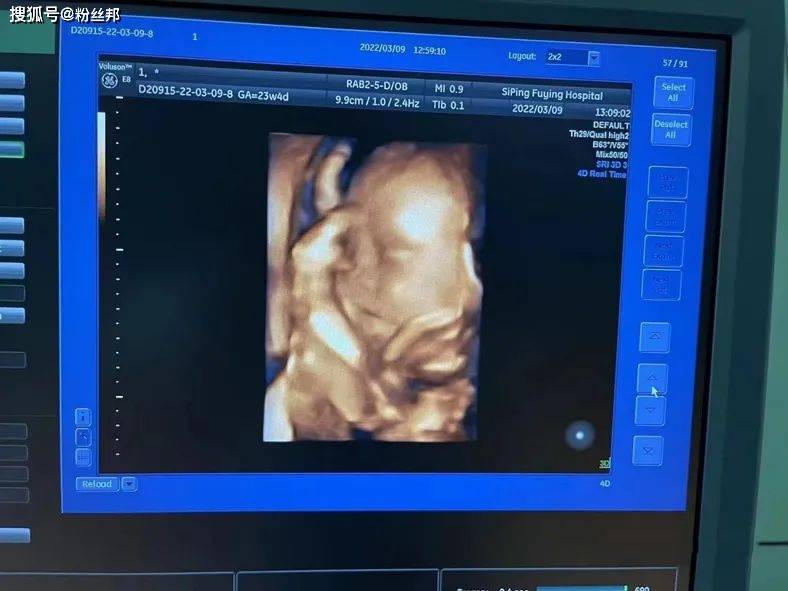

而就在近日,阿哲发布动态晒出老婆二胎的孕检照片,直言“老二真帅”。

据了解还有三个月“哲嫂”孙珊珊就会生产,在阿哲直播的时候有透露过,老婆二胎预产期是6月份左右,并且二胎怀的也是一个男孩儿。